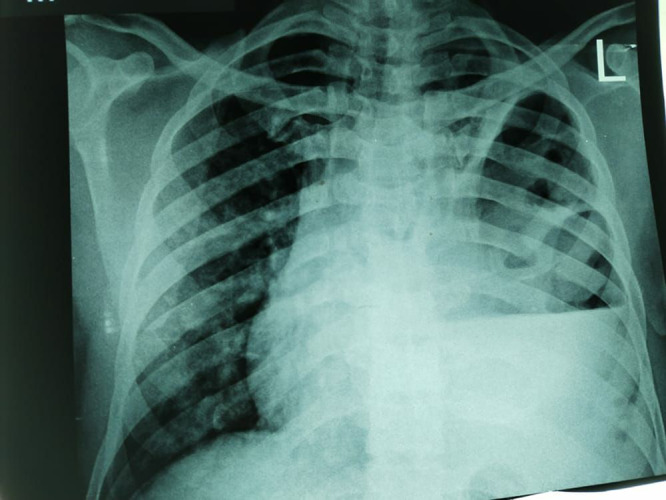

Case report: A 45-year-old man from Eastern Sudan presented to the emergency department complaining of breathlessness, cough stained with blood, and chest pain one month before his presentation. Also, he complained of high-grade fever for two weeks associated with sweating. Diagnosis of hydropneumothorax was made and a chest tube was inserted, two days later we found three adult A. lumbricoides worms in the chest drain.

Conclusion: The patient was treated with Albendazole 200 mg, orally twice, daily for seven days, he improved and was referred to a cardiothoracic surgeon for more assessment. Our study highlights that internal medicine specialists should know about pleural ascariasis when patients present with respiratory signs and symptoms, especially in A. lumbricoides endemic regions like Eastern Sudan.